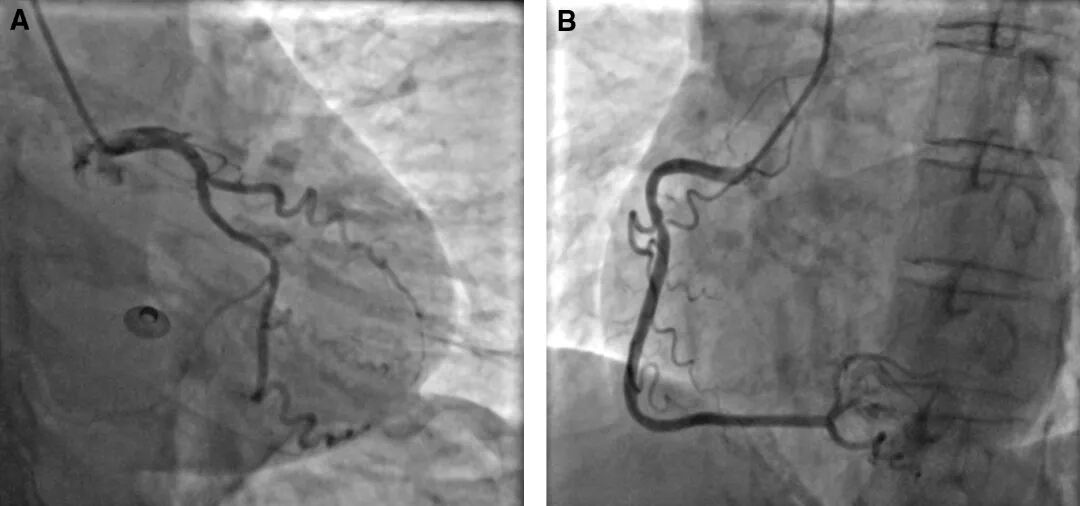

图2 冠脉造影

注:(A)左前降支与左回旋支冠脉造影:左前降支开口部70%狭窄,左前降支近段完全(100%)闭塞,左回旋支远段70%狭窄。(B)右冠状动脉造影:右冠状动脉近段40%狭窄。